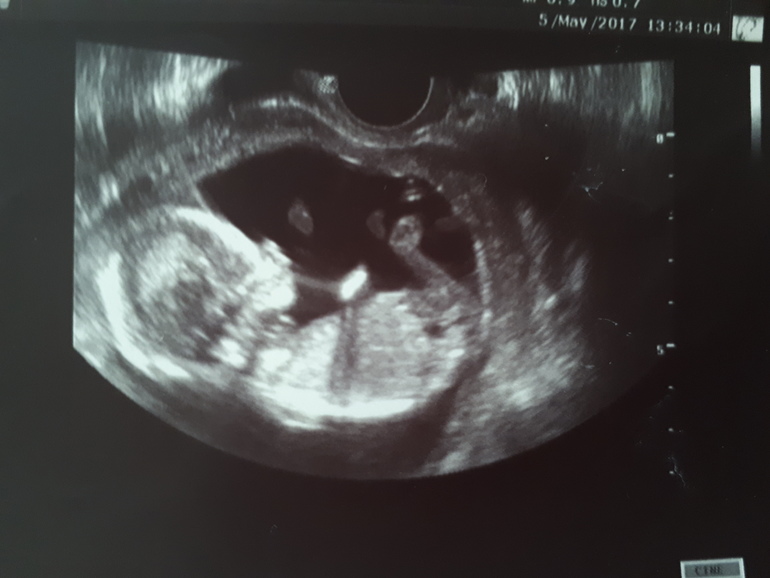

Сын! Наш Никитосик!

Лежал, трогал носик, засовывал кулочек в ротик, дергал пуповину, наматывал её на ножку))) усердно пинал, пытаясь оттолкнуться:) котёночек мой:)